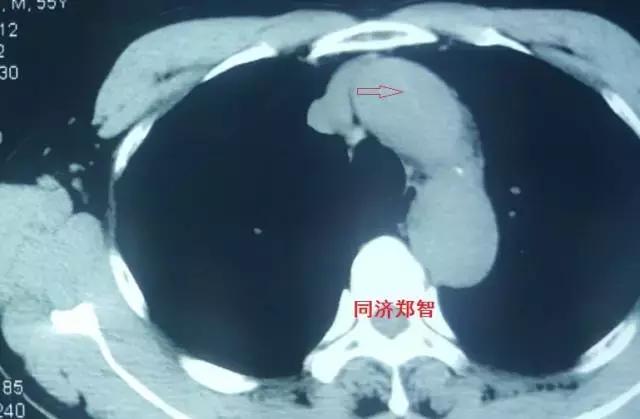

第一招 血管直径增大征

这个征象比较好识别,当主动脉夹层形成巨大的夹层动脉瘤时,通过胸片、平扫CT、彩超等也能初步诊断主动脉病变。

病例四

腹部平扫CT提示腹主动脉增宽,CTA证实为腹主动脉局限性夹层(红箭头所示)。